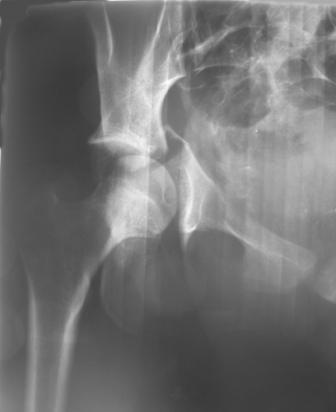

30/11/04 |  30/11/04 |  30/11/04 |  14/12/04 |  14/12/04 |  14/02/05 |  14/02/05 |  21/02/05 | Уважаемые коллеги! Случилось вторичное смещение вертлужной впадины после операции. Посоветуйте, что делать. Пациентка 18 лет. Травма 19.11.04. D.s.: Закрытыый Т-образный высокий перелом правой вертлужной впадины. Закрытый перелом м\мыщелкового возвышения левой б\берцовой кости. 9.12.04 операция - открытая репозиция, остеосинтез переломам вертлужной впадины. 30.12.05 выписаны на амбулаторное лечение с рекомендациями не вставать на правую ногу. 14.02.05 при контрольном осмотре на Р-граммах выявлено вторичное смещение передней колонны. Клинически подвывиха нет, имеется умеренная приводящая контрактура правого тазобедренного сустава, гипотрофия мышц н\конечностей. Госпитализирована в травмотделение. Выполнено КТ. Имеется смещение передней колонны кнутриЮ диастаз 8 мм. Посоветуйте пожалуйста, что предпринять в данной ситуации.